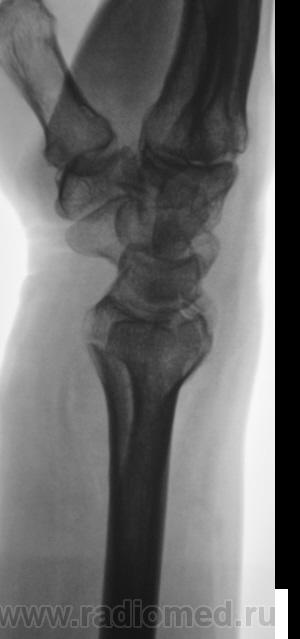

Пациент направлен на рентгенографию лучезапястного сустава.

Пациент направлен на рентгенографию лучезапястного сустава хирургом, была травма. После производства снимков стали допытываться у пациента, о "факте более ранней травмы". Все бесполезно - не помнит, не знает ....

Ваше мнение, уважаемые коллеги?